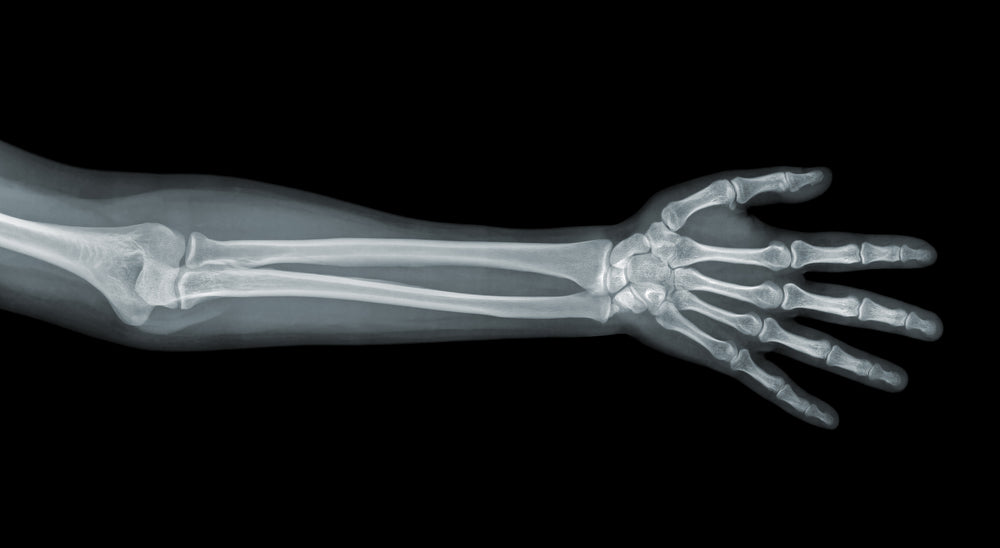

Arms, legs, head, teeth or chest areas being x-rayed, do not expose the foetus to direct x-ray beams. If an x-ray of these areas is essential, a lead apron is placed over the stomach to shield your baby.

Lower abdomen, stomach, pelvis or kidney areas do expose the foetus to direct beams, however the levels of radiation the foetus receives is not of concern. Of course an x-ray of this nature would only be performed if completely necessary.